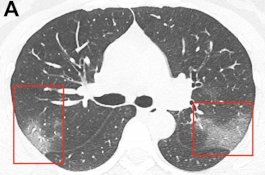

Foto X-Ray Menunjukkan Efek Mengerikan Coronavirus pada Paru-paru Pasien

Health

- 02 Februari 2020 08:59